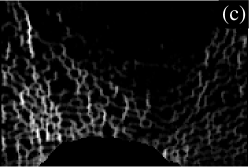

III.6 Illustration

To illustrate the analytical method, we now present the results in visual form for an enlarged region near the bottom (posterior) of the slice in Fig. 1. The enlarged region of the original image is shown in Fig. 3(a). Parts (b) to (e) of Fig. 3 show directional strand strengths, and part (f) shows the final node strength plot. Each directional strand strength plot shows the sum of two strand strengths at every pixel, in opposite directions: east/west; north/south; northwest/southeast; and northeast/southwest. In each of the directional strand strength plots, the strands in the given direction are shown with the highest intensity, but most of the trabeculae are still visible, even if faintly. In contrast, in the node strength plot (part (f)), most of the trabeculae are invisible. This is because of the subtraction of the minimum strength constant. In this example, there are almost no nodes in the right half of the image. This correctly describes the micro-architecture of the original image in that region, which contains many trabeculae but few that cross each other to make a lattice-like micro-architecture. The left half of the image contains many nodes. Notice that, in the node strength plot, the nodes seem to be thicker than in the original image. This is because the trabeculae in the original image are actually slightly thicker than they appear, the outer pixels being dimmer (i.e. lower CT values) and thus not easily registered by the eye. Since the outer pixels near the apparent nodes in the original image are almost as well-connected as pixels in the centres of the nodes, they have large node strengths, and are very visible in the node strength plot.